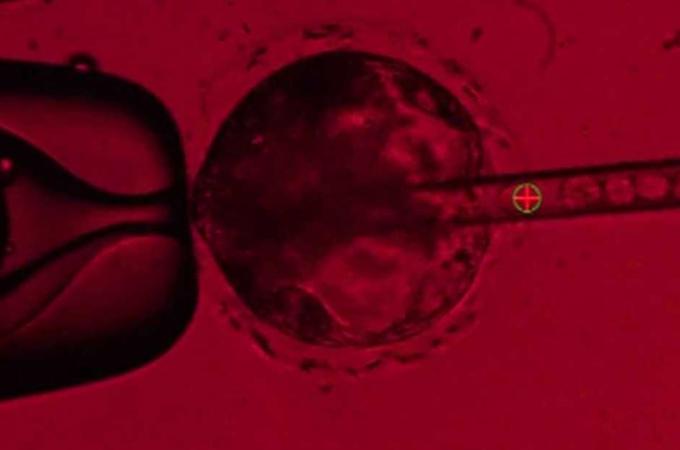

Kde sehnat orgány na transplantace? Můžeme je vypěstovat v prasatech!